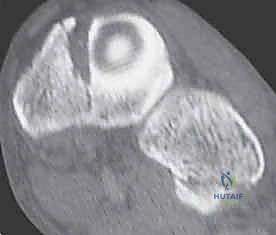

3. التصوير المقطعي المحوسب (CT Scan)

في الحالات المعقدة، أو عند التخطيط للجراحة، يُعد التصوير المقطعي أداة لا غنى عنها. فهو يوفر صوراً ثلاثية الأبعاد تفصيلية للعظام، مما يسمح باكتشاف الكسور الدقيقة جداً (Micro-fractures) وتقييم مدى الإزاحة في المفاصل، وهو أمر حيوي لنجاح أي تدخل جراحي.